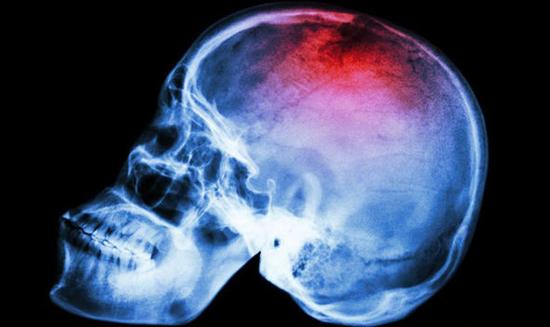

Canavero博士也声称,接到许多英国志愿者的申请信息。他声称手术的第一步将是冰冻大脑和身体,阻止脑细胞死亡。然后切开脖子,将关键的动脉和静脉将连接到管子上。在进行移植之前将切断患者的脊椎。

当肌肉和血液供给成功连接之后,病人将昏迷一个月时间来限制新移植头颅的活动,同时将通过电刺激让脊椎新连接得到强化。这位野心勃勃的医生相信,物理疗法将让接受头部移植手术的病人在一年内下床走路。(过客编译)